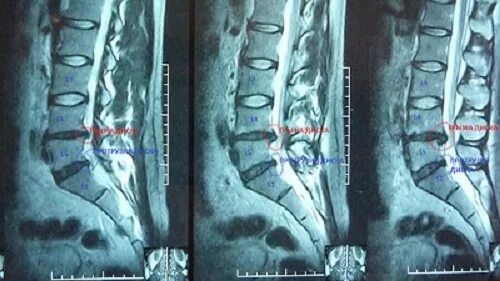

Межпозвоночная грыжа можно ли вылечить без операции